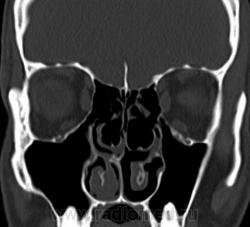

1. Эктопия зуба?

2. Хронический гайморит?